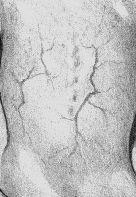

Рис. 45. Цирроз печени. Венозная сеть на спине

Определяется наличием хронического холестаза. Характерны кожный зуд, желтуха, остеопороз, кровоточивость, стеаторея. На коже появляются сосудистые звездочки, следы расчесов, пигментация. Печень всегда увеличена, плотная. Появляются изменения костной системы – остеопороз, увеличение эпифизов костей, патологические переломы позвоночника. Частым осложнением цирроза является пептическая язва двенадцатиперстной кишки. Для вторичного билиарного цирроза характерны приступы желчной колики, ускорение СОЭ, повышение температуры тела.